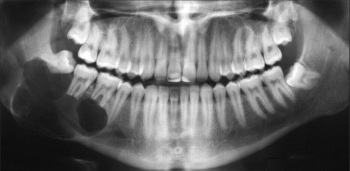

Hình X-quang răng hỗn hợp ở trẻ đang độ tuổi mọc răng vĩnh viễn. Hình cho thấy các mầm răng vĩnh viễn nằm trong xương hàm.